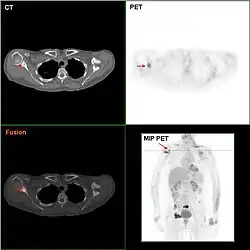

Die Positronen-Emissions-Tomographie ist derzeit keine Routinemethode, kann jedoch eingesetzt werden, um nach dem Primärtumor bzw. dessen Metastasen zu suchen, wenn dieser mit anderen Methoden nicht gefunden werden kann.

Knochenszintigramme, Computertomographien, Röntgenaufnahmen der Lunge, Sonographien der Leber und ggf. Kernspintomographien dienen dazu, nach Metastasen zu suchen, also die Ausbreitung der Erkrankung zu erkennen. Angesichts der Tatsache, dass die PET/CT bis auf die MRT-Hirn- und Brustuntersuchung genauer ist und zugleich auch andere Krebserkrankungen ausschließen kann, erscheint die PET/CT sinnvoller als Knochenszintigramme, Computertomographien, Röntgenaufnahmen der Lunge und Sonographien der Leber zusammen.